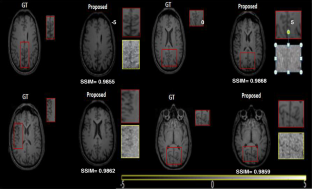

Fig. 8